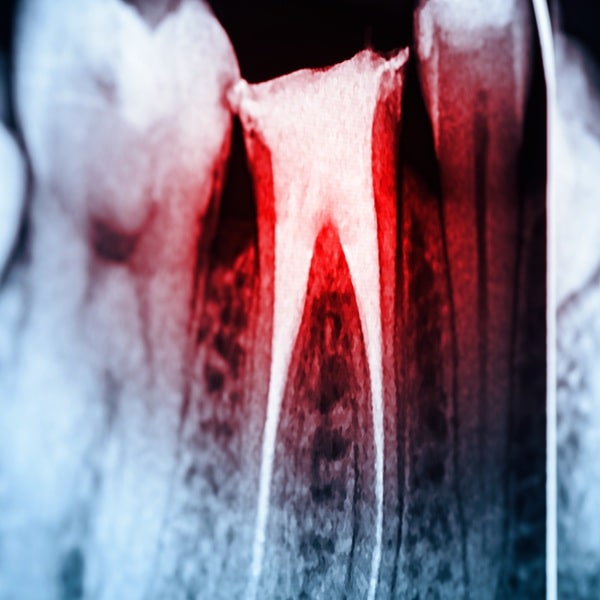

We start with an X-ray to see the shape of the root and confirm what’s going on. Then we carefully remove the infected tissue from inside the tooth, clean and disinfect the area, and seal it with a protective material. After that, we restore the tooth with a filling or crown to bring back strength and shape.